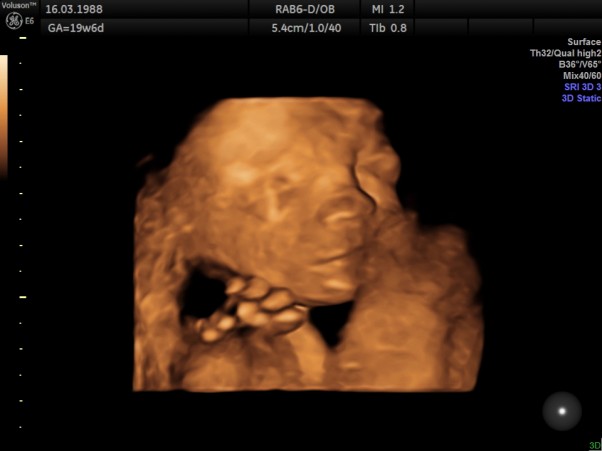

USG 4D

Na ten dzień czekałam z wielką niecierpliwością, dzisiejsza technologia daje nam tak wiele możliwości, Bardzo byłam ciekawa jak wygląda nasz synuś. Przed wyjściem na badania powiedziałam do męża: Zobaczysz kochanie nasz mały to na pewno zakryje się rączkami i zrobi nam na "złość" :)

Kolejne moje przeczucie potwierdzone:) Nie dość że spał, to jeszcze tyłem. Pan doktor mocno nagimnastykował się aby się synu chociaż trochę przekręcił. Raczej nie dla nas a dla zbadania serduszka. Ale dzięki temu mogliśmy chociaż ciut podglądnąć, cóż tam w tym brzuszku się kryje.